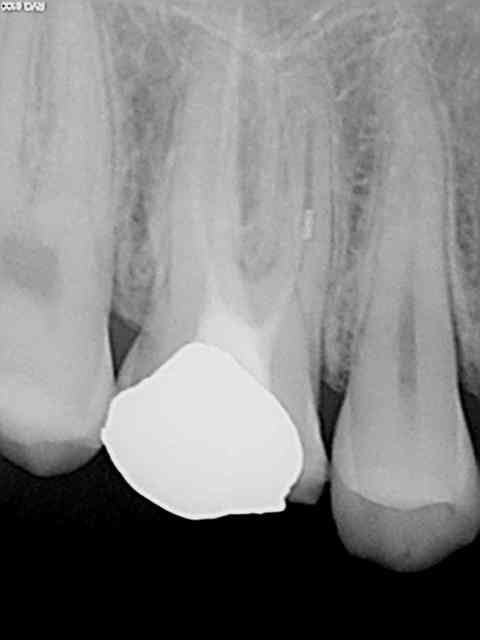

Exemples routiniers d'une banalité affligeante......

R24 kuiaas - Eugenol

R26 urwzsa - Eugenol

R8 q2dwjf - Eugenol

R14 d5xuv9 - Eugenol

Pepsi tmi4vp - Eugenol